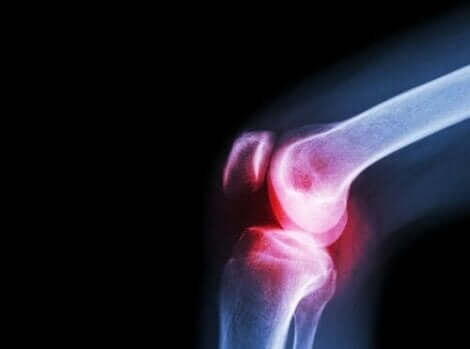

العرض الآخر التقليدي لحالة الذئبة الحمامية الجهازية هو ألم المفاصل. يظهر ذلك بسبب التهاب المفاصل الناتج عن الاستجابة المناعية الذاتية التي يتم إطلاق العنان لها في الجسم. تطور التهاب المفاصل يحدث في صورة نوبات حادة، فتظهر فترات خالية من الألم وأخرى تتسم بآلام شديدة.